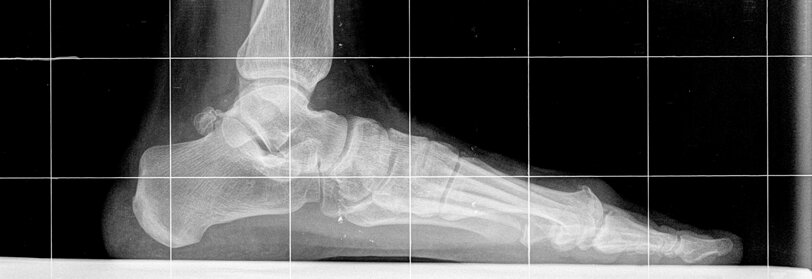

L'alluce valgo e' la piu' comune affezione dell'avampiede ed e' caratterizzata dalla deviazione laterale dell'alluce a livello dell'articolazione metatarso-falangea associata ad un aumento dell'angolo tra primo e secondo metatarso (varismo del I metatarso), alla lussazione dei sesamoidi ed alla protrusione dell'eminenza mediale. Puo' essere causato da molti fattori. Tra i fattori intrinseci e' fondamentale la componente genetica, infatti piu' del 60% degli affetti presenta casi analoghi in famiglia. Le calzature sono la principale causa estrinseca, in particolare se con tomaia stretta e tacco alto. Anche il piede piatto puo' predisporre all'alluce valgo. Il paziente lamenta dolore in corrispondenza dell'esostosi ed al di sotto della prima articolazione metatarso-falangea, il dolore aumenta con la scarpa indossata. Spesso puo' essere associato ad arrossamento e tumefazione. L'esame principale e' rappresentato dalle radiografie dei piedi sotto carico nelle due proiezioni, utilizzate per misurare i vari parametri, che contribuiscono a guidare nella scelta del tipo di trattamento da adottare. Gli obiettivi dell'intervento comprendono il sollievo del dolore con una correzione della deformita' ed il ripristino della corretta biomeccanica dell'articolazione. Gli interventi di correzione possono agire solo sulle parti molli, interessare il primo metatarso, o esclusivamente la falange prossimale dell'alluce. Nei casi piu' gravi si puo' ricorrere all'artrodesi, bloccando l'articolazione. Nel periodo post-operatorio il carico e' concesso immediatamente con una calzatura particolare che consente l'appoggio sul retropiede. I pazienti vengono controllati una volta a settimana per la medicazione della ferita chirurgica ed il rinnovo del bendaggio, che dovra' essere mantenuto all'incirca per 6 settimane. Tale periodo varia in funzione del tipo di tecnica adottata per la correzione.